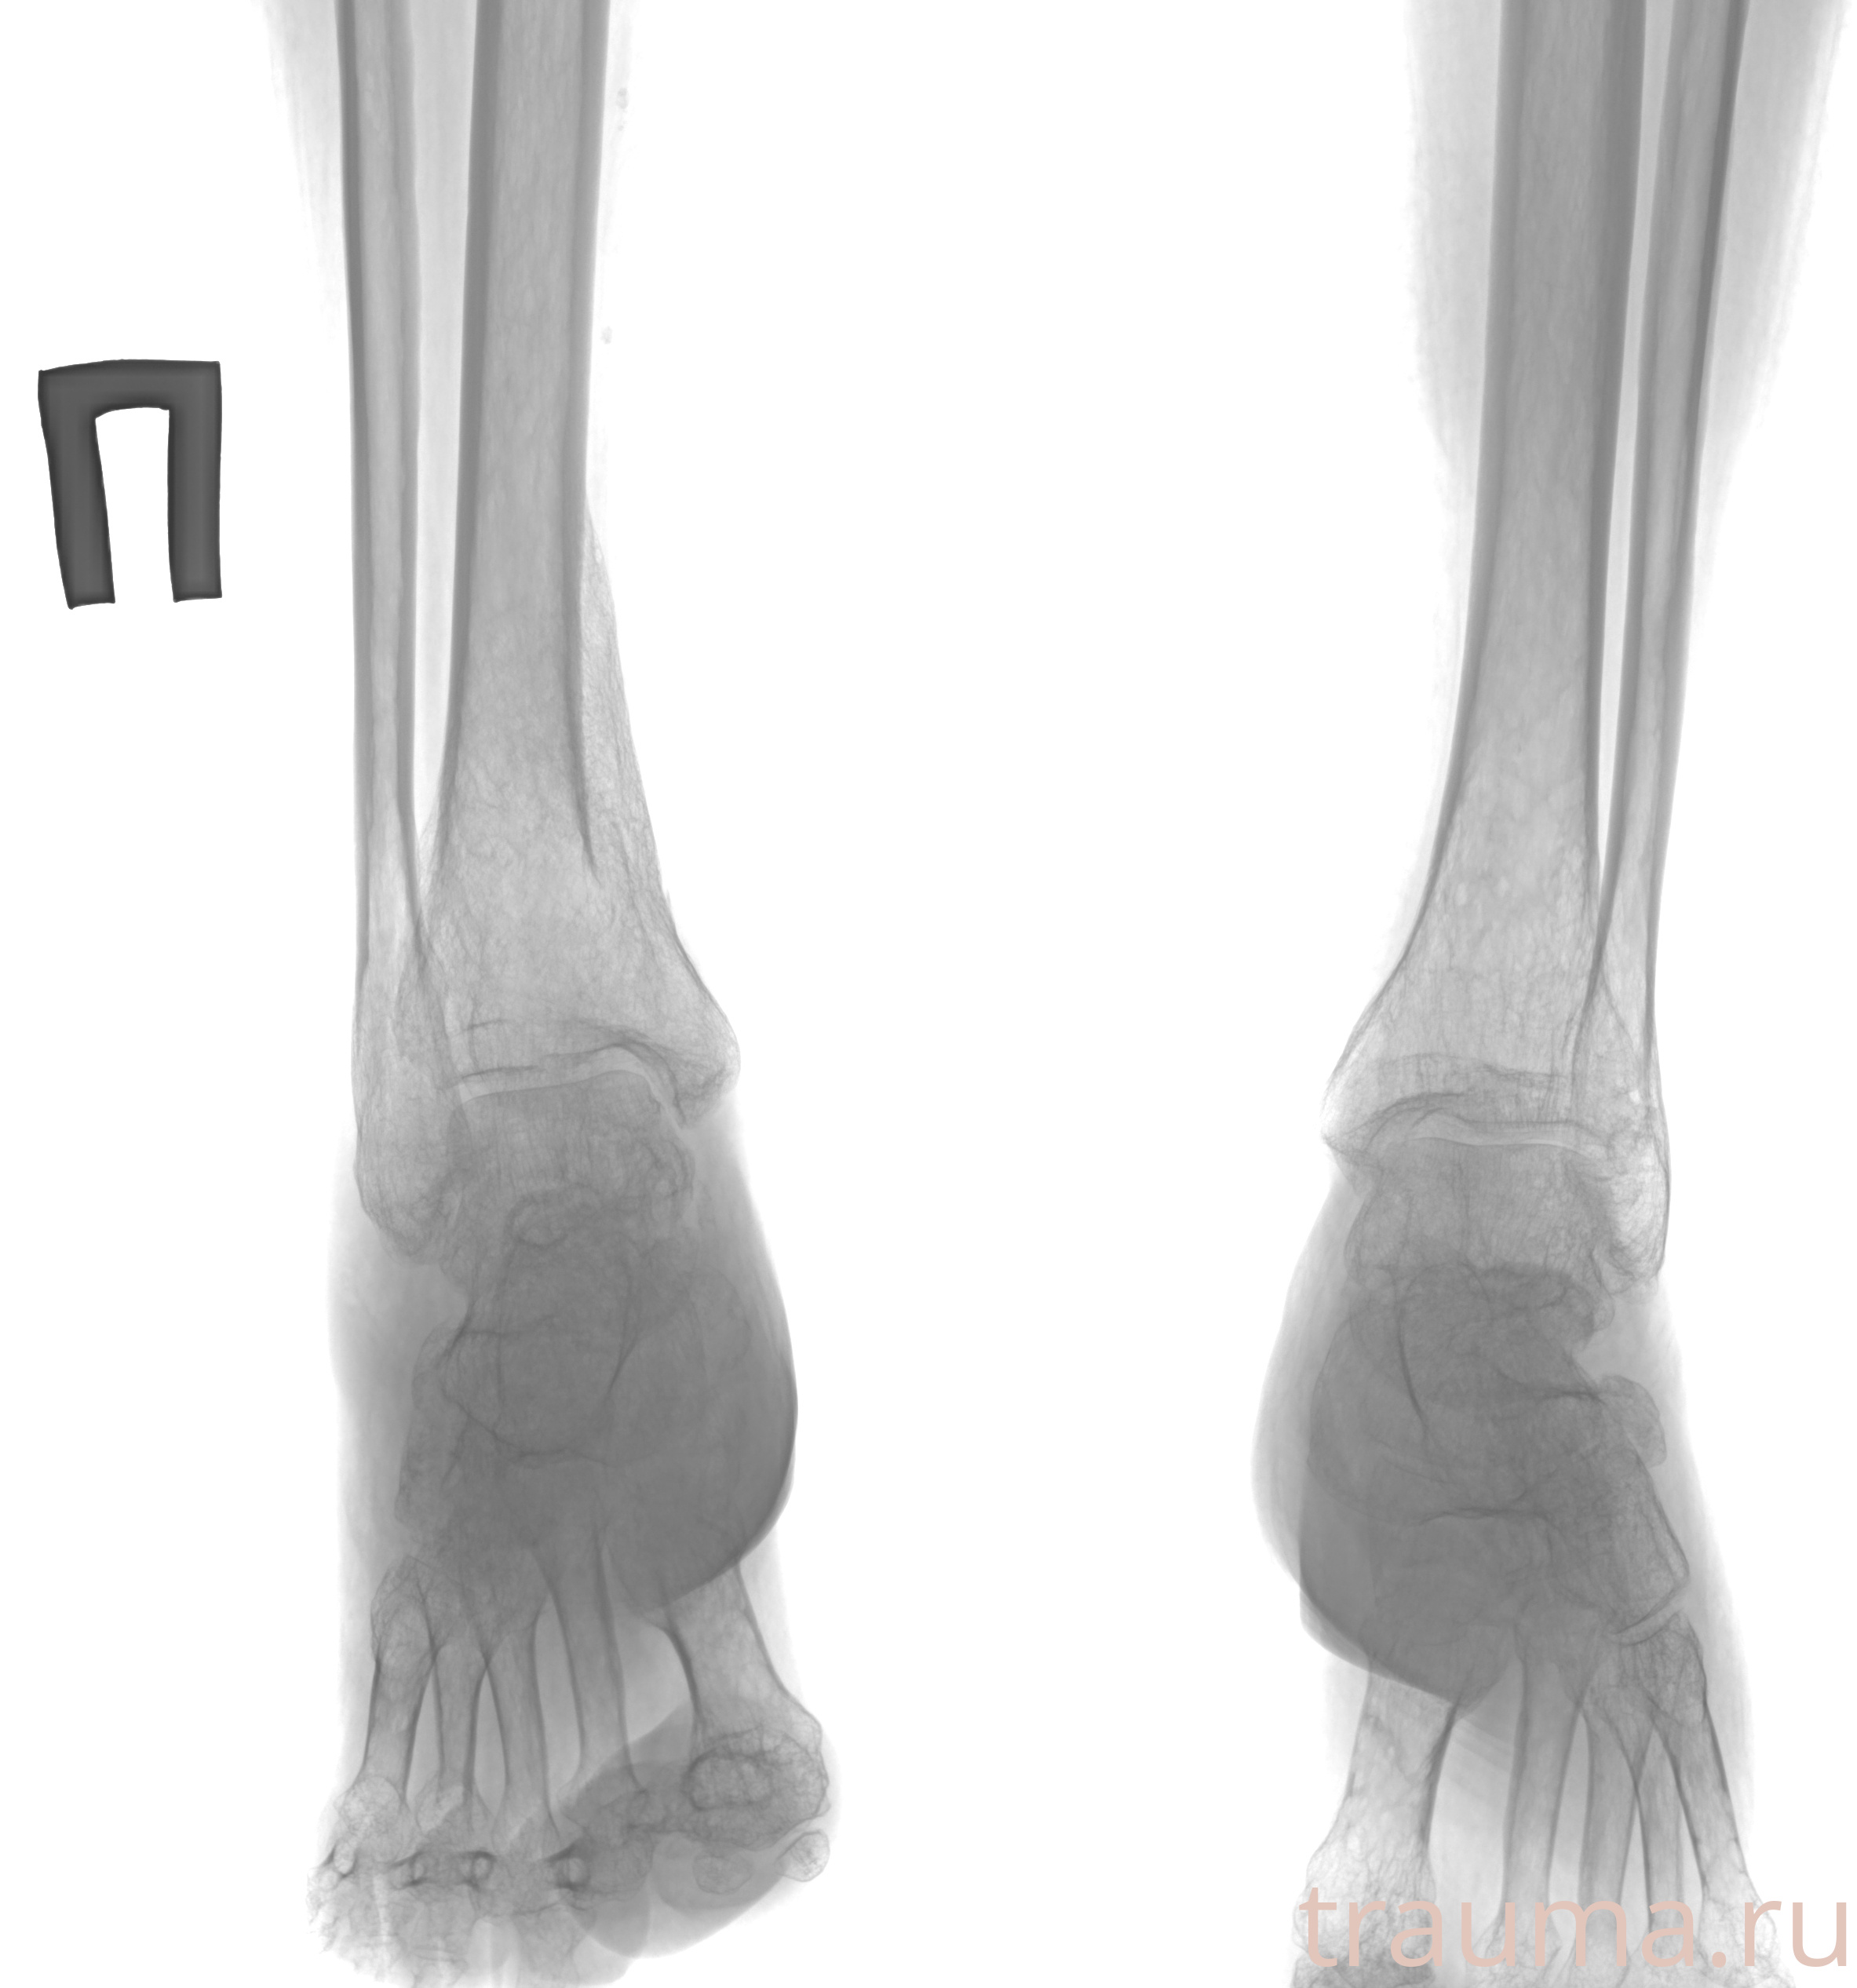

Рентгенограммы

Рентген на дому: по вашему адресу приезжает врач-рентгенолог, травматолог-ортопед с мобильным рентгеновским аппаратом, проводит диагностику травмы или заболевания, делает необходимые рентгенограммы, дает рекомендации по дальнейшему лечению. Получить качественные снимки в домашних условиях возможно благодаря уникальной методике, разработанной МосРентген Центром для института  Склифосовского